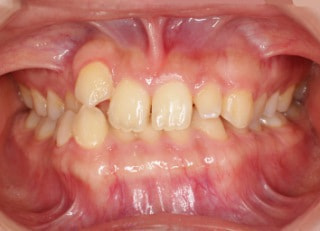

治療後(2年11ヶ月後)